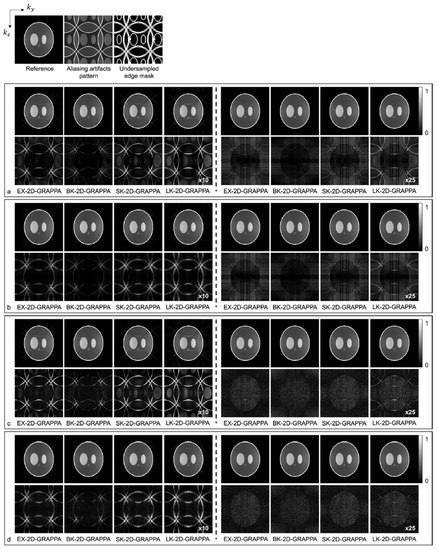

3.2. Computer Simulations

4. Results